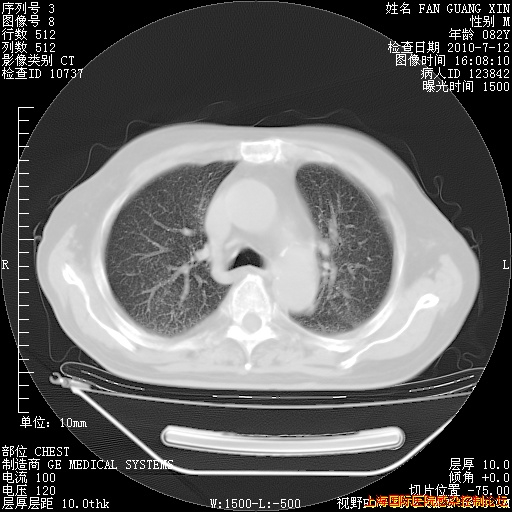

今天复查CT

今天CT

整整相隔30天的肺部CT好像有所好转啊。甲强龙减量第3天,需要观察体温。